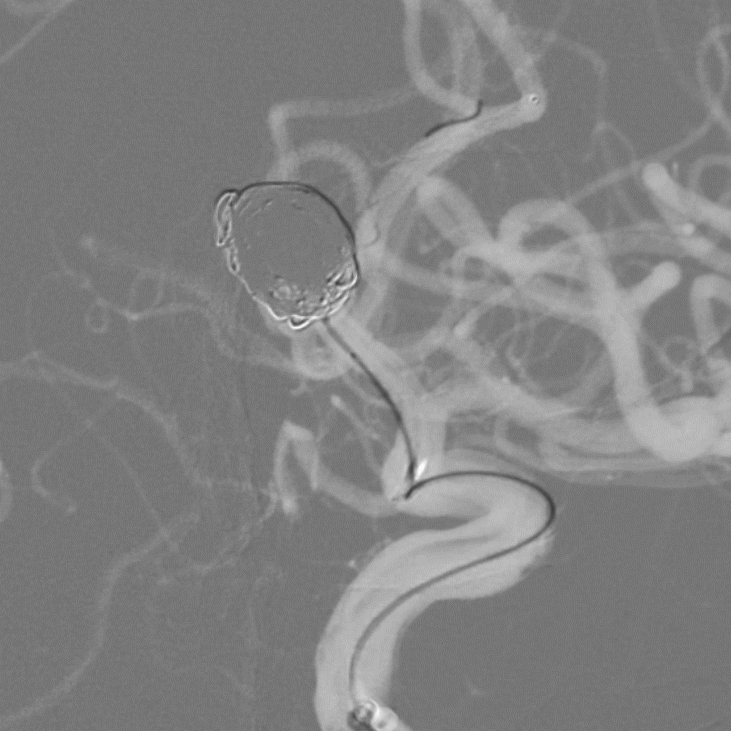

➢术前造影

通过术前影像已知患者前交通大型动脉瘤,测量动脉瘤11.68mm*9.68mm*5.45mm,动脉瘤体较大且患者一侧大脑前动脉发育纤细,术中需要保证支架置入血管通畅和分支血管通畅。

目前大型动脉瘤修复血流导向装置是比较好的选择,此病例动脉瘤在前交通段,在此处使用血流导向装置,可能会发生A1段的穿支血管缺血并发症,为避免缺血事件计划采用经典支架辅助弹簧圈栓塞动脉瘤。

考虑到术后动脉瘤闭塞率和动脉瘤愈合时间,此病例选用金属覆盖率较高的编织型支架辅助栓塞,A1段的血管直径需要双系统操作可能存在困难,所以选用可经0.017导管释放的Leo Baby支架即可保证支架的金属覆盖率,也可保证术中操作的简便性。